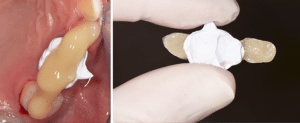

Se référant à la nouvelle DV fixée par le mock-up antérieur et l’enregistrement avec les clés, le laboratoire (LM2M, Paris) usine en PICN les 4 overlays molaires et les 4 veneerlays prémolaires (Fig.9).

Fig.9 : Restaurations postérieures en composite.

Avant d’être essayés en bouche, ils sont stabilisés sur le modèle avec une très fine couche de cire orthodontique et une clé linguale des antérieures mandibulaires est réalisée en silicone.

Le protocole de collage (Fig.10a, b) d’un PICN est le même que celui d’un composite indirect classique. Au niveau de l’intrados : sablage alumine 50 microns, fine couche de silane et séchage pendant 3 minutes.

Fig.10a, b : Collage des restaurations indirectes postérieures.

Fig.10b.

Au niveau de la dent : sablage alumine 27 microns ou nettoyage minutieux de la préparation (ponce humide), mordançage amélaire et application du système adhésif.

Pour l’assemblage on utilise une colle sans potentiel d’adhésion, ou un composite de restauration chauffé ou un composite semi-fluide chargé (type Gaenial Universal Injectable, GC).

Dans notre cas clinique, les restaurations ont été assemblées avec le système adhésif Scotchbond Universal (3M, ESPE) et le composite semi-fluide Gaenial Universal Injectable (GC) teinte A2. Les trois restaurations de chaque secteur ont été collées en même temps afin d’éviter qu’un excès d’une première restauration collée ne gêne l’insertion de la suivante. Si on préfère coller un par un, ou deux par deux (en laissant la dent du milieu par exemple), il faut protéger les préparations avec du téflon pendant le collage de la prothèse collatérale.